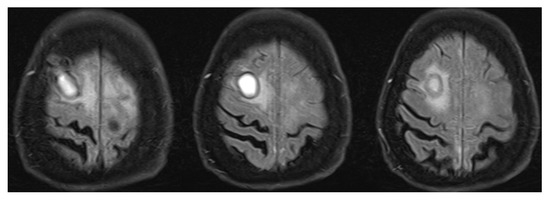

Analysis of Treatment Influence on Kidney Function and Brain Non-Contrast MRI Vascular Manifestations of Systemic ANCA-Associated Vasculitis with Renal Involvement

Background: Antineutrophil cytoplasmic antibody-associated systemic vasculitis (AAV) most often involves the kidneys, upper airways and lungs, and peripheral and central nervous systems (PNS, CNS). However, in contrast to PNS, the involvement of the CNS is rarely taken into account in the recognition and assessment of systemic vasculitis, probably because of nonspecific symptoms such as headaches and dizziness, aphasia, memory disorders, or mood changes. In addition, it is not clear whether treatment of systemic vasculitides reduces cerebral vascular alterations. In this study, we aimed to evaluate the effects of AAV treatment on vascular and vasogenic alterations in the brain in patients with acute vasculitis onset with renal involvement. Methods: Twenty-nine patients (17F, 12M, age 60.4 ± 9.8) with AAV relapse with renal involvement were included in the study. The initial baseline assessment and the second evaluation, performed 12.6 ± 2.5 months after the beginning of immunosuppressive treatment, included clinical, neurological, and renal function assessments, along with a brain MRI. Results: Compared with baseline, improvement in clinical, neurological, and renal function was observed during the second clinical evaluation. A significant reduction in the occurrence of vascular dilatation and narrowing in secondary (37.9% vs. 17.2%; p = 0.031) and tertiary (37.9% vs. 10.3%; p = 0.008) cerebral vascular branches was observed. However, the number of vasogenic cerebral white matter lesions detected on the FLAIR sequence increased significantly (36.0 vs. 48.0%; p < 0.001). Conclusions: Intensive immunosuppressive treatment of acute-onset systemic AAV with renal involvement decreases disease activity, improves kidney function, and decreases central nervous system vascular but not vasogenic alterations. Full article